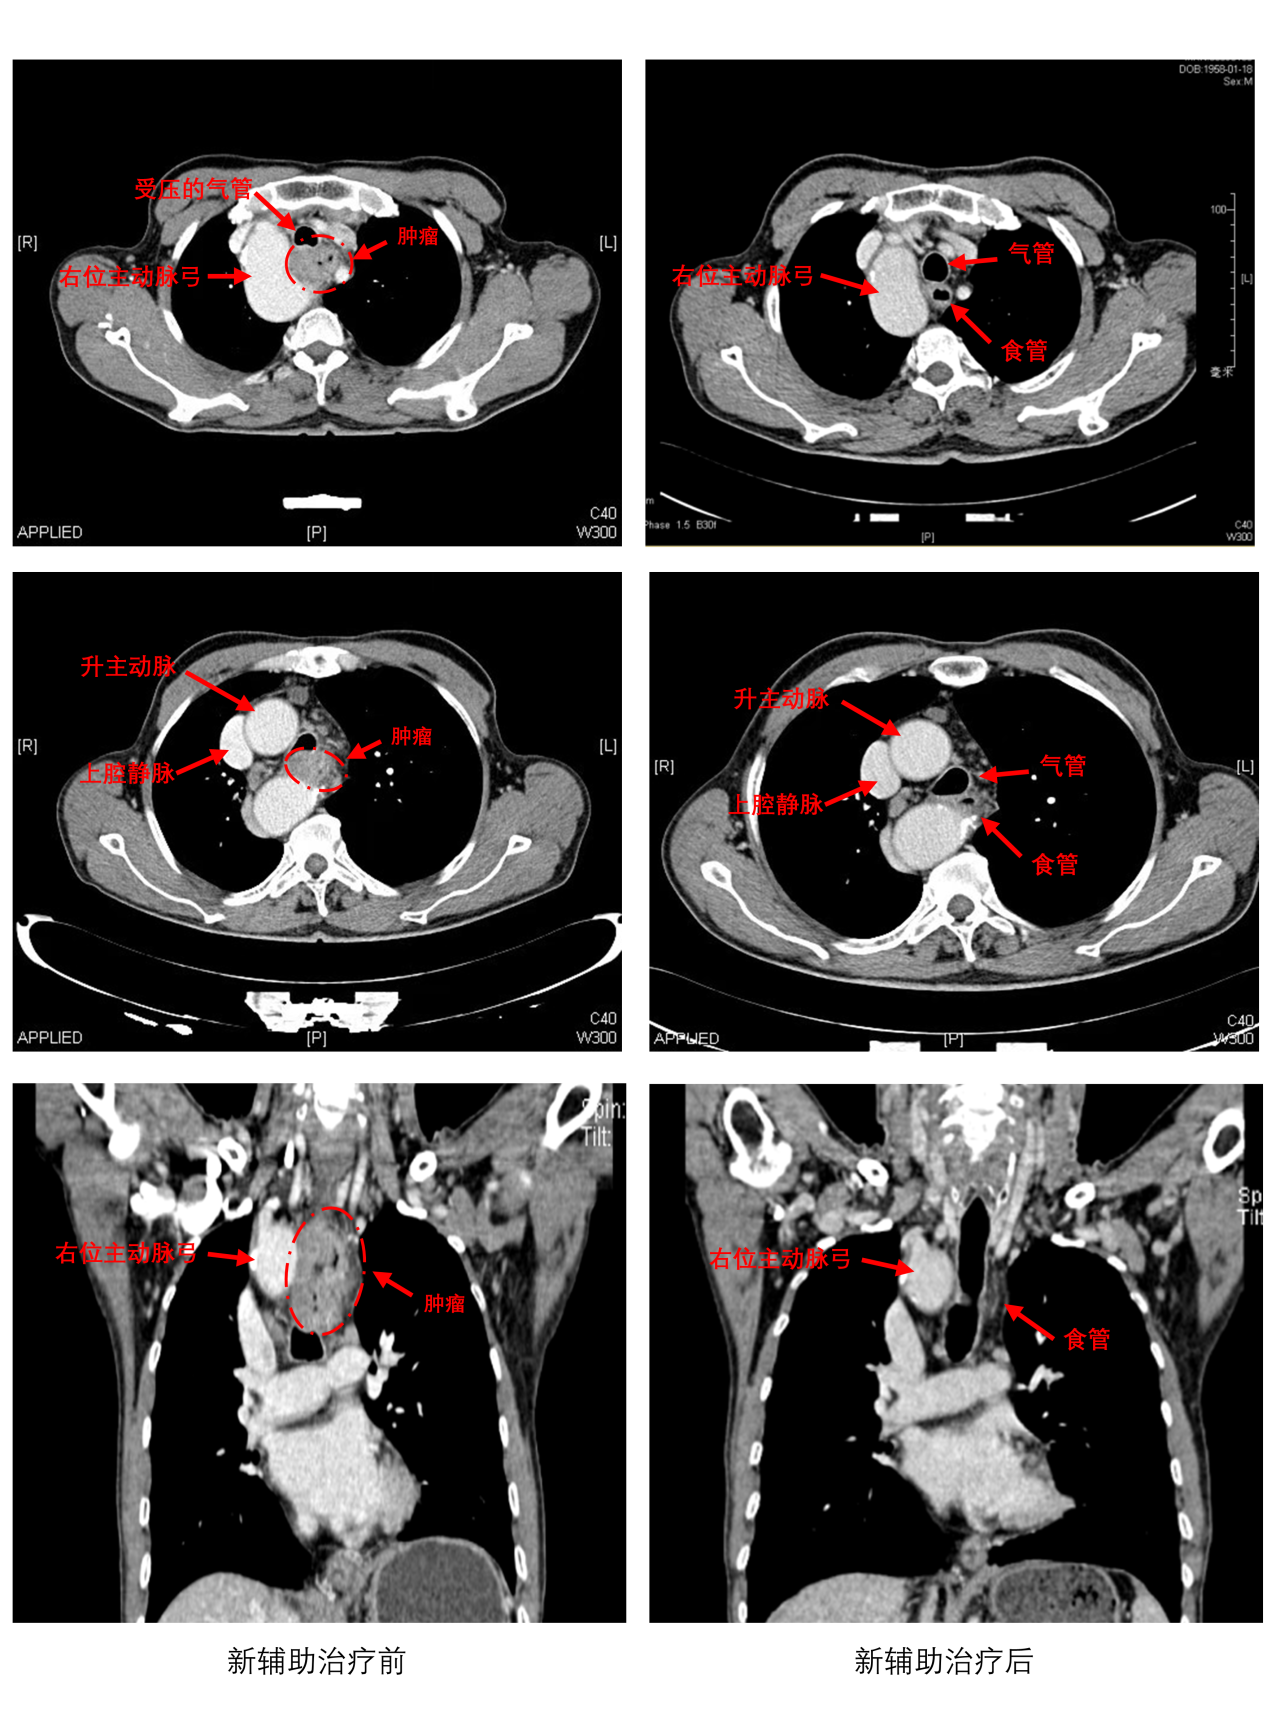

2023年秋,老乐因吞咽困难就医,确诊为颈段食管癌(仅占食管癌5%),且已至局部晚期。更凶险的是,CT检查发现他竟患有右位主动脉弓——一种罕见的先天性血管畸形,导致上纵隔空间极度狭窄,肿瘤紧贴咽喉与异常血管,传统手术极易残留癌细胞或引发大出血。

3周期术前新辅助“化疗+免疫”治疗,肿瘤缩小超过50 %,为手术创造条件;

CT血管成像立体还原血管与肿瘤位置,提前规划手术路径;